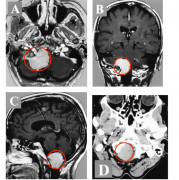

近几十年来,核磁共振成像技术(iMRI)已成功应用于 神经胶质瘤 和垂体腺瘤的根治性手术,并与计算机神经导航技术相结合。然而,只有少数研究报道了该工具用于手术治疗 鞍旁脑膜瘤...

鞍上 脑膜瘤 常发生于鞍结节、交叉沟和蝶窦平面,占全部颅内脑膜瘤的5%至10%。这些脑膜瘤通常是良性的,生长缓慢,直到肿瘤生长导致关键的神经血管结构受压,如视交叉的后移位和...